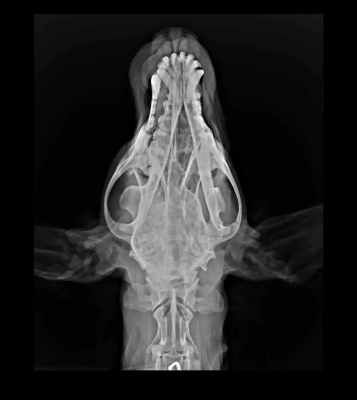

06.03 - посещение хирурга-стоматолога.

Результаты посещения ошеломляюще плохие:

5. рентген челюсти.